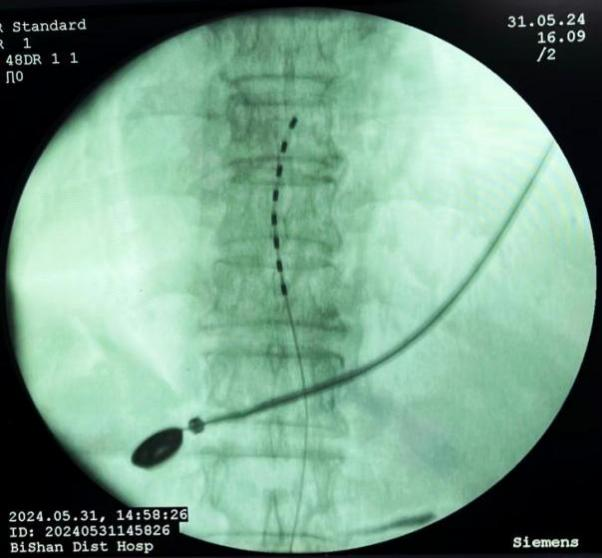

脊髓電刺激植入術(shù):將電極植入脊柱附近硬膜外腔,通過電流刺激脊髓,阻斷疼痛信號傳至大腦,有效治療慢性頑固性神經(jīng)痛。

圖片

脊髓電刺激植入術(shù)